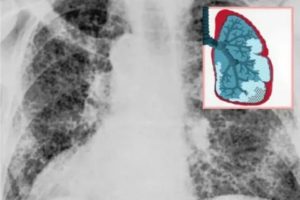

Визуально после пневмонии он определяется на рентгеновских снимках в виде фиброзных тяжей и рубцов – полосы затемнения. Это приводит к уменьшению дыхательной поверхности легких и развитию хронической дыхательной недостаточности.

Фиброзные тяжи на рентгеновском снимке

По результатом обследований наблюдаются фиброзные очаги (тяжи, рубцы) и значительное снижение функции легких.